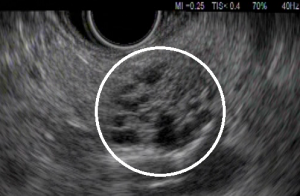

Usually serous cysts are benignant and the most common type is serous cystadenoma. Serous cystadenoma is featured with microcysts and is discovered by chance. Abdominal pain may result from large serous cystadenoma.